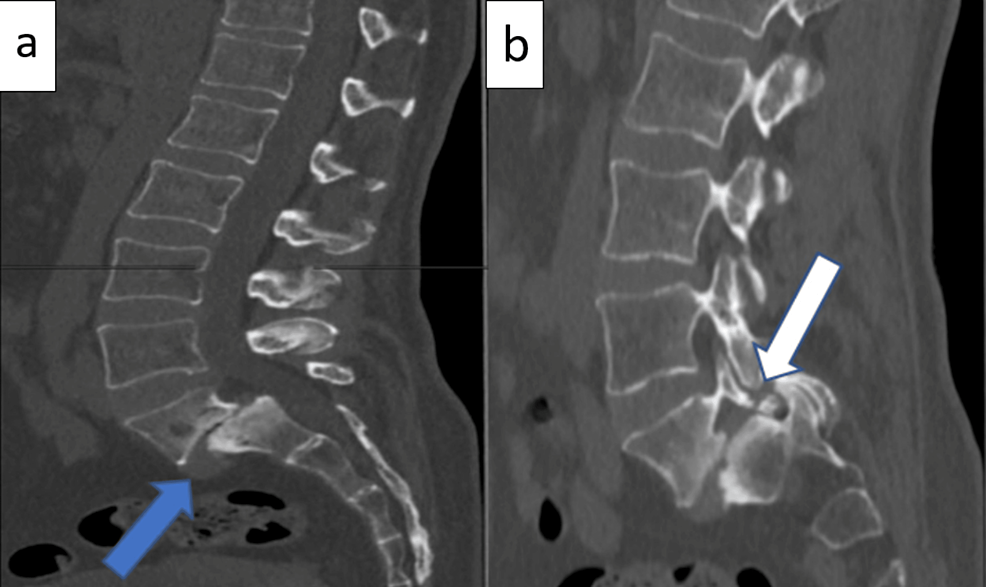

Diagnostic Imaging

X-rays, MRIs, or CT scans provide a very definitive way to assess the degree of slippage of your vertebral segments. Your radiologist will assign a grading from I (minimal) to V (severe).